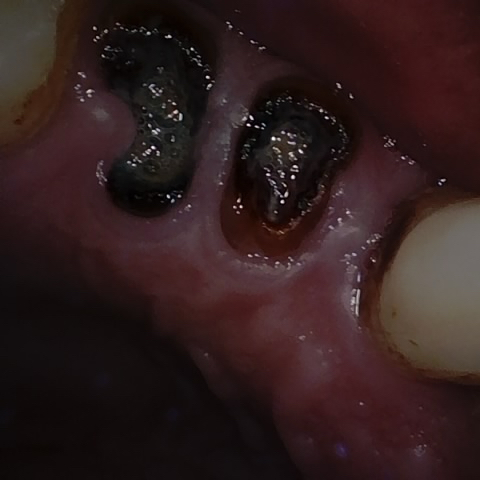

Annotated as "Good"